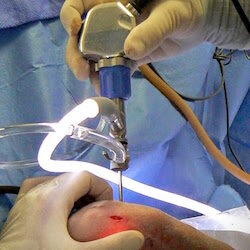

Arthroscopic Surgery

Minimally invasive "keyhole" incisions contribute to a faster recovery. Magnification improves diagnosis and facilitates treatment. Indications including developmental diseases of the elbow (dysplasia) & shoulder e.g. OCD , coronoid disease (FMCP).